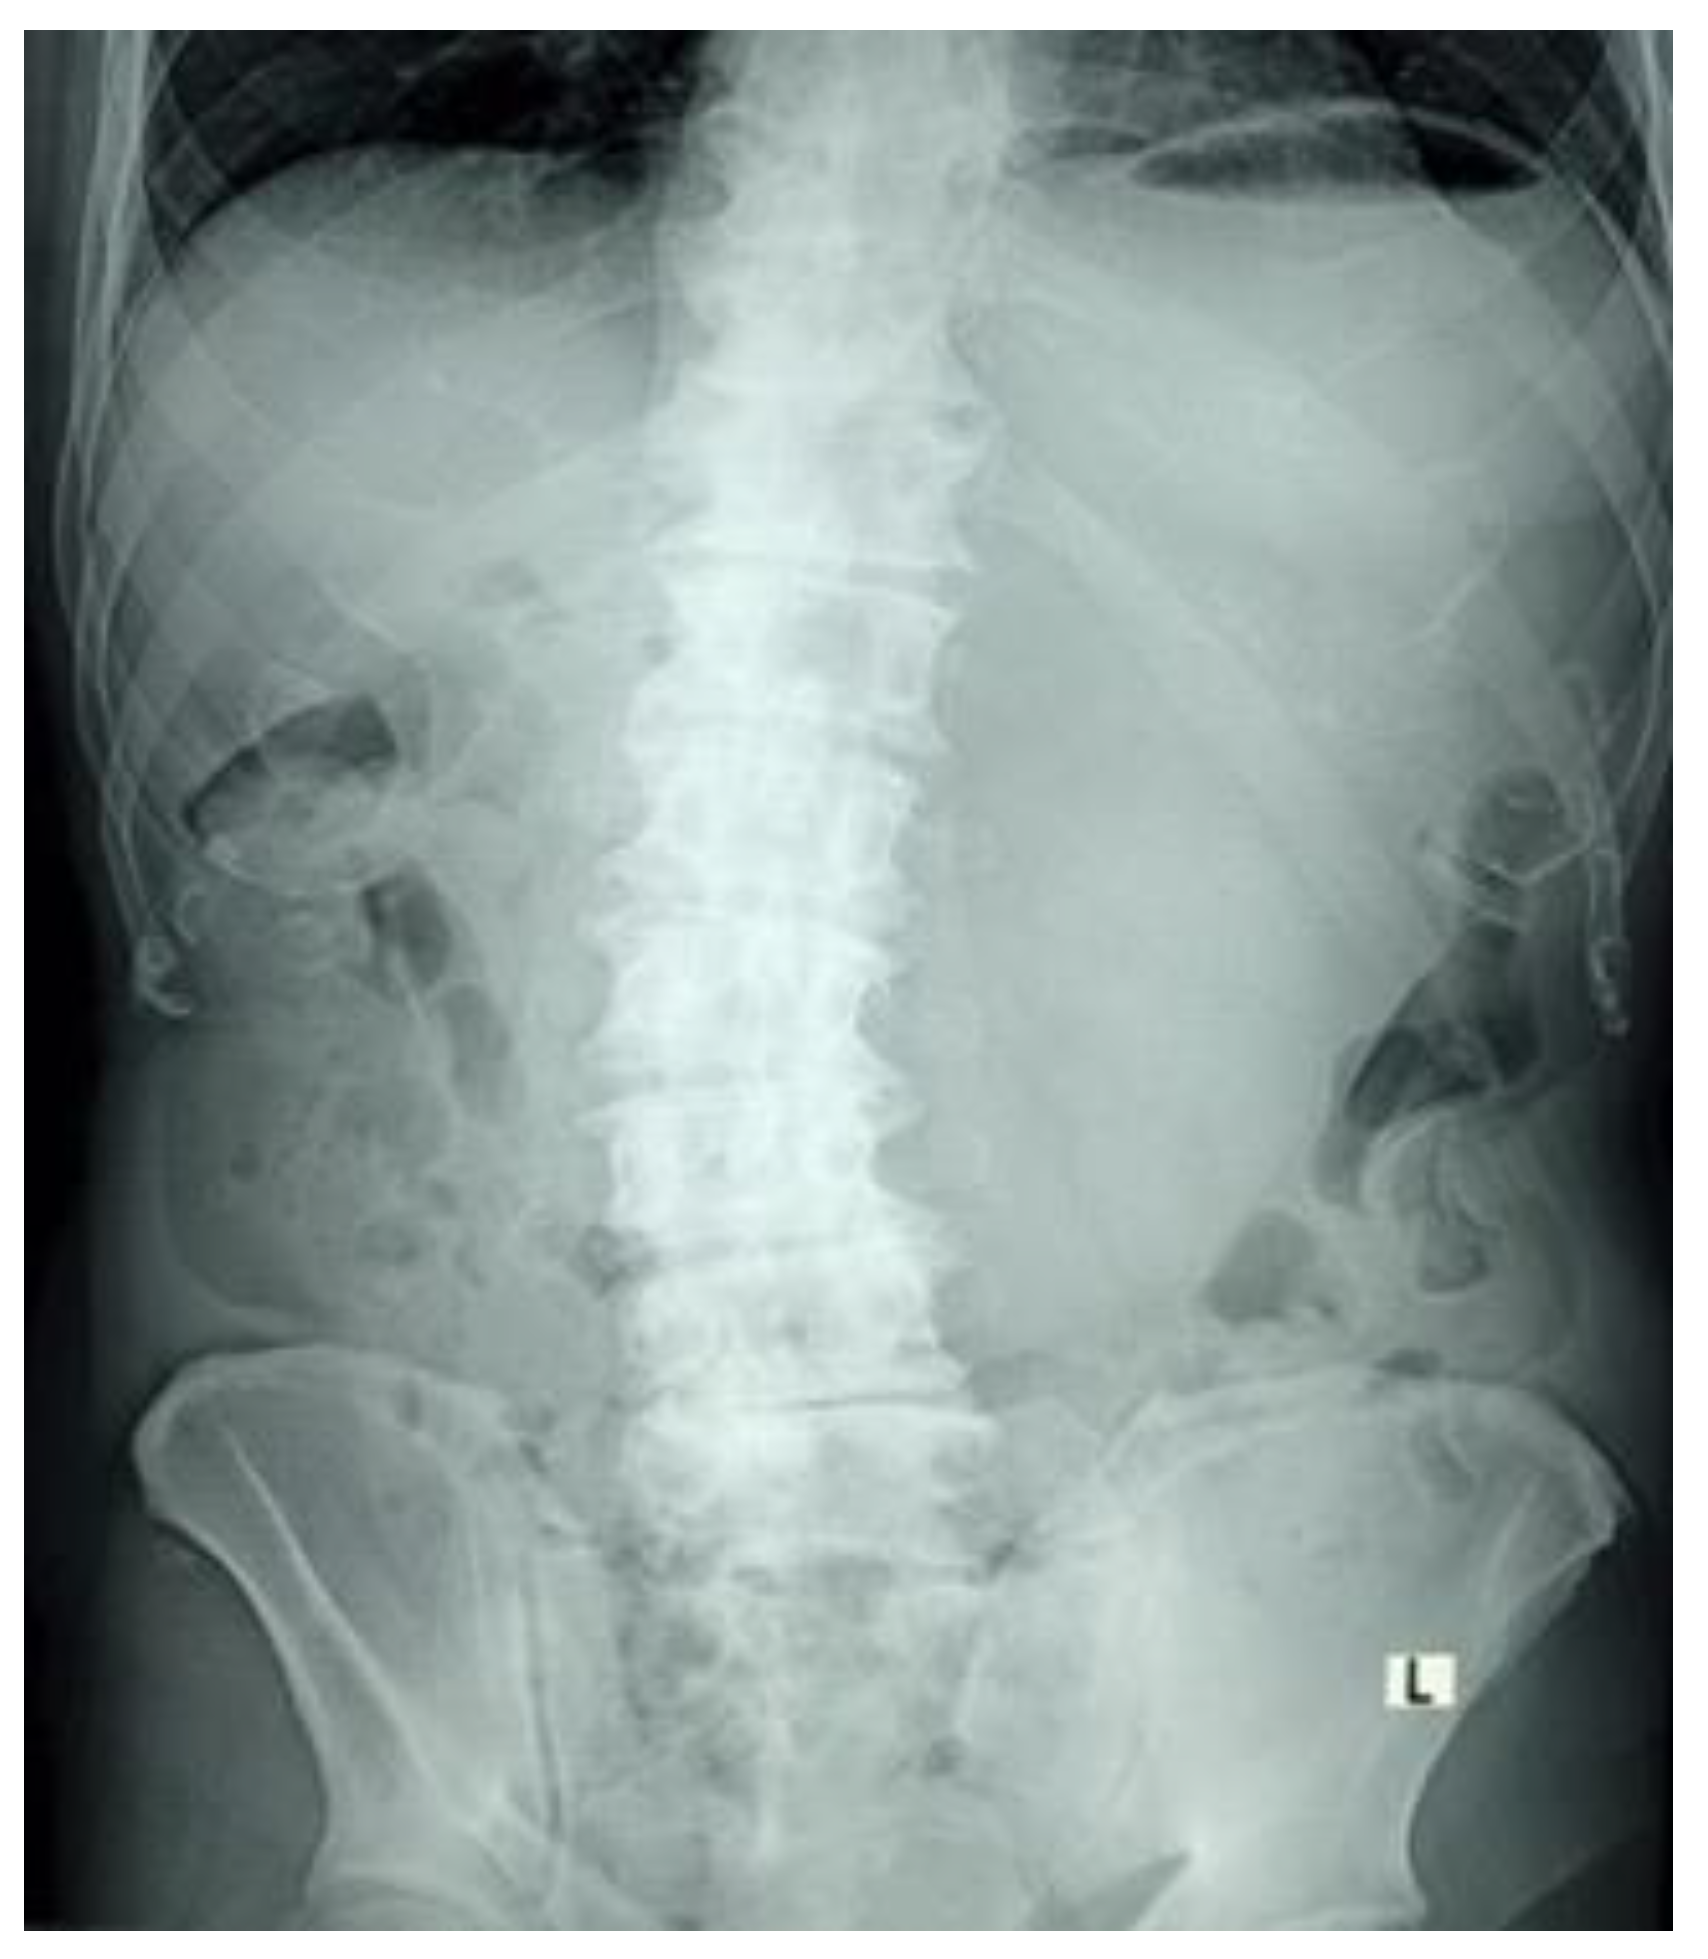

Figure 1 An abdominal radiograph showed pneumobilia and an enlarged gastric bubble of a 81-year-old man presented to the emergency department with epigastric pain, vomiting, anorexia and obstipation for 3 days. Physical examination was notable for a painful epigastric tenderness. Laboratory examinations revealed a white blood cell count of 22.1 (3.4-9.7)(10*9/L).

Figure 5 and Figure 6 Subsequent computed tomography with intravenous contrast material confirmed pneumobilia with direct visualization of a tract between the gallbladder and the duodenum and a 25 mm gallstone impacted in the duodenal bulb (long arrow) causing gastric distention so diagnosis of cholecystoduodenal fistula was made. Bouveret’s syndrome is characterized by gastric outlet obstruction (GOO) secondary to cholecystoduodenal fistula. [1,2] Fistula formation is favoured by the long history of cholelithiasis, the repeated episodes of acute cholecystitis, the large size of the gallstones (2–8 cm), the female gender and advanced age ( > 60 years ). Morbidity and mortality rates are high, estimated at 60% and 12%–30% respectively, due to the advanced age and the comorbidities of the patients. [3] Patients usually present with non-specific signs and symptoms of GOO, including nausea and vomiting in 87%, abdominal pain in 71%, hematemesis in 15%, weight loss in 14% and anorexia in 13%. [4] The radiologic features of gallstone ileus are the classical Rigler’s triad that consists of pneumobilia, dilated small bowel and an ectopic gallstone. [5] A plain abdominal X- ray is diagnostic in about 50% of cases and may demonstrate intestinal obstruction, pneumobilia, an ectopic gallstone, alteration in the position of the previously observed stone or two air fluid levels in the right upper quadrant secondary to air in the gall bladder. [6] US may show the gallstone sufficiently large to be apparent. The fistula may also be visualized if filled with fluid or air. Pneumobilia and a dilated stomach may also be seen with US. [7,8] CT is the best imaging technique used to search for Rigler’s triad that is specific to gallstone ileus and with it’s 93% sensitivity, 100% specificity, and 99% accuracy is needed for definitive diagnosis. [9] Up to 20% of the gallstones may be isoattenuating when MRI is indicated because it detects Rigler’s triad in nearly all cases where it was present. [10]

Figure 1. Plain abdominal radiography.